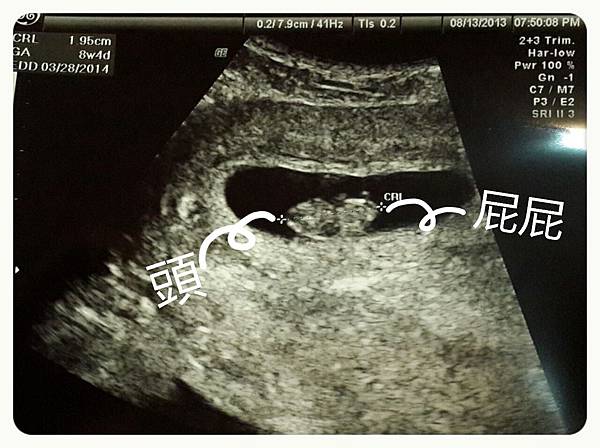

第一次產檢的日子終於來了,雖然距離上次才短短兩週的時間,但迫不急待的相見歡總令人期待。當醫生的超音波一照,橢圓狀物立刻現身,醫生指了指頭在哪裡屁股在哪裡,這次的心跳聲清楚的讓我有點感動有點心安,每分鐘158下跳動喲!!洛克馬現在是1.95公分大,下次見面又要隔一個月囉!!醫生要我忍耐噁心和反胃,我也只能硬著頭皮說好~